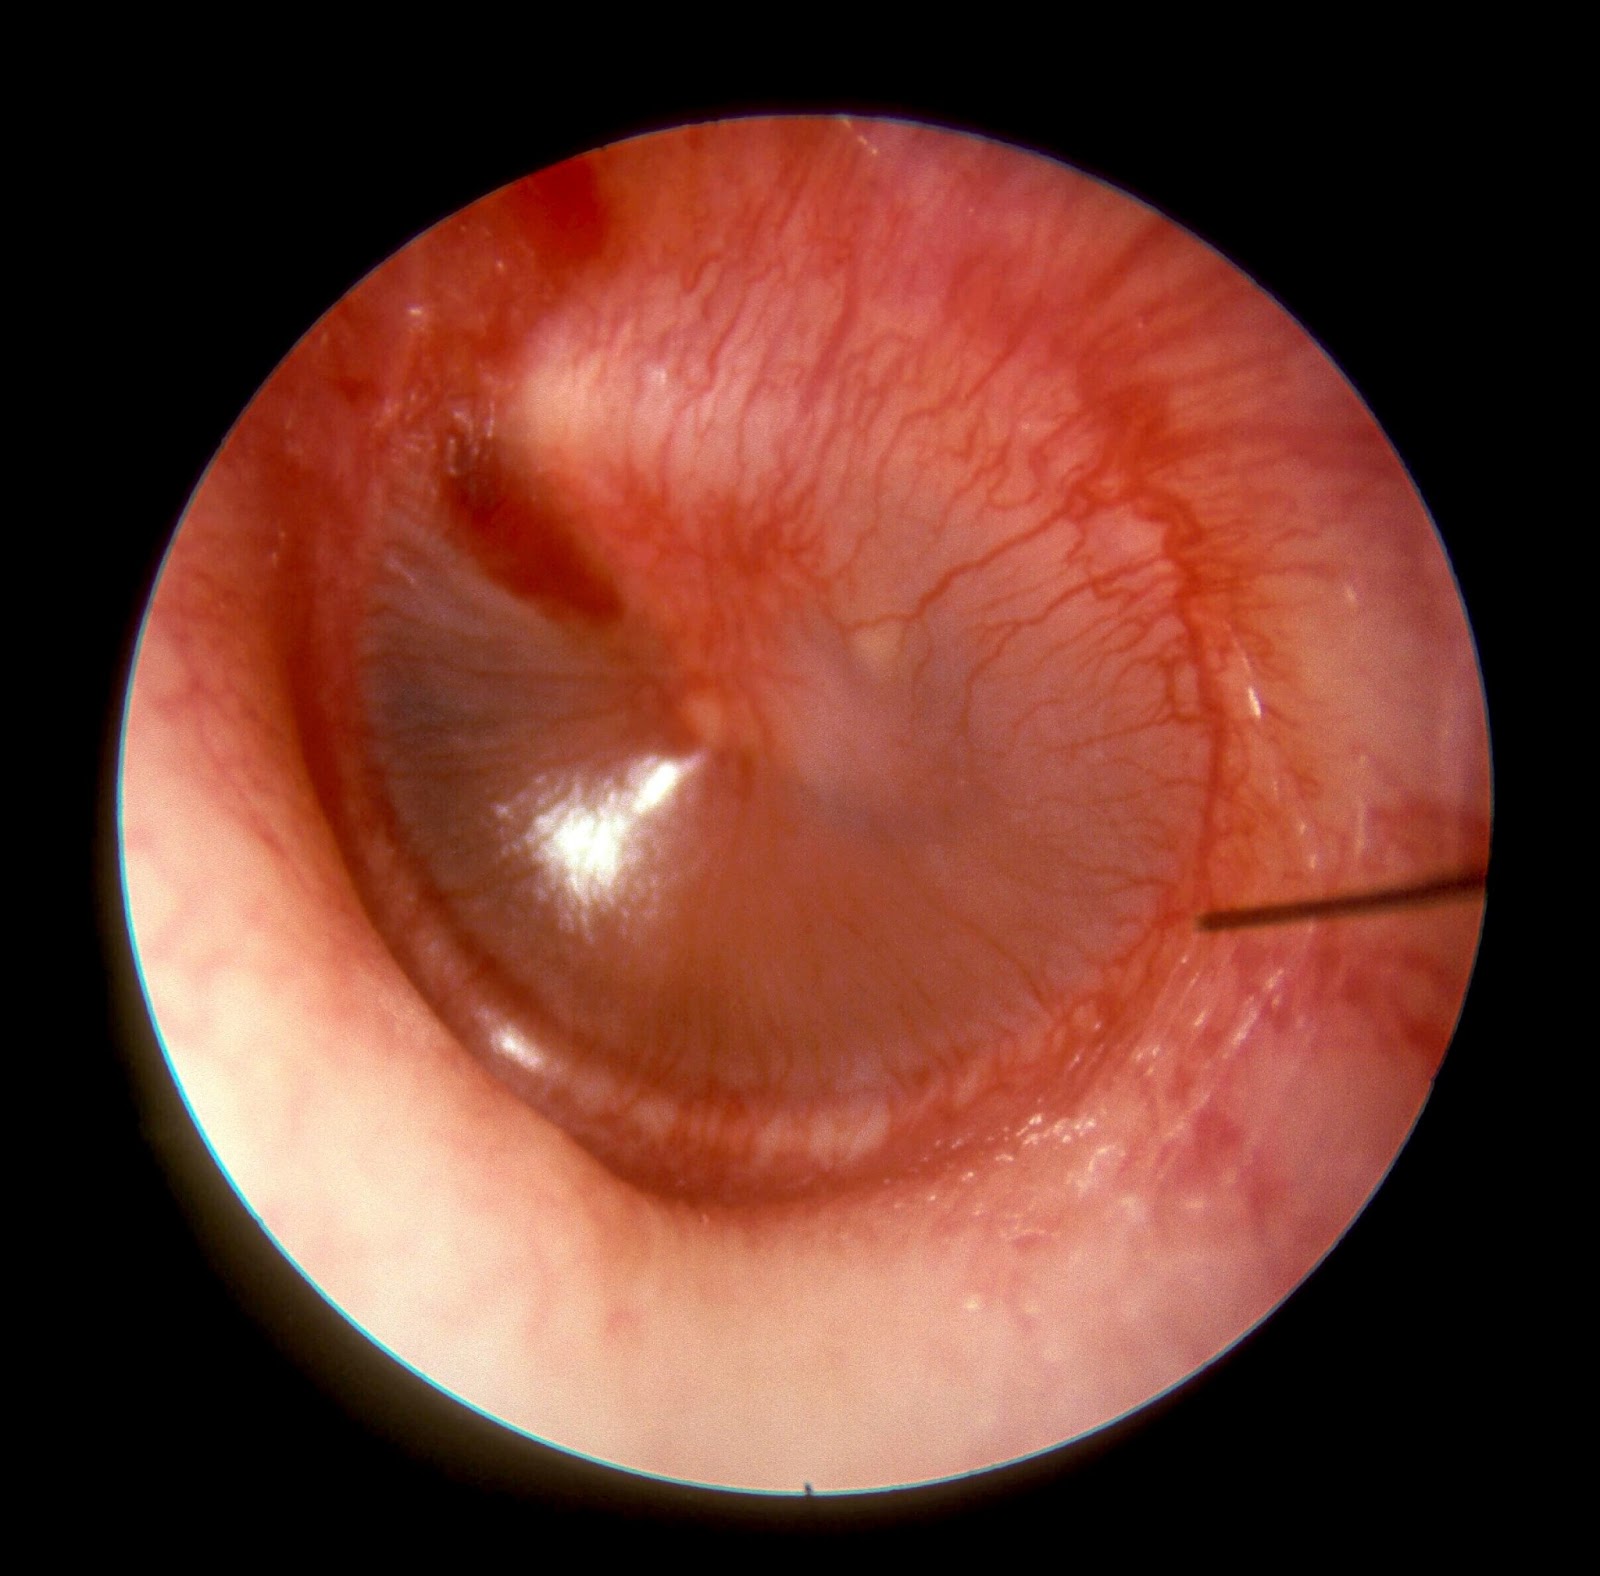

Otitis Media Aguda

Es una infección aguda de la mucosa del oído medio y cavidades vecinas. Frecuentemente se asocia a una infección viral o bacteriana del tracto respiratorio superior